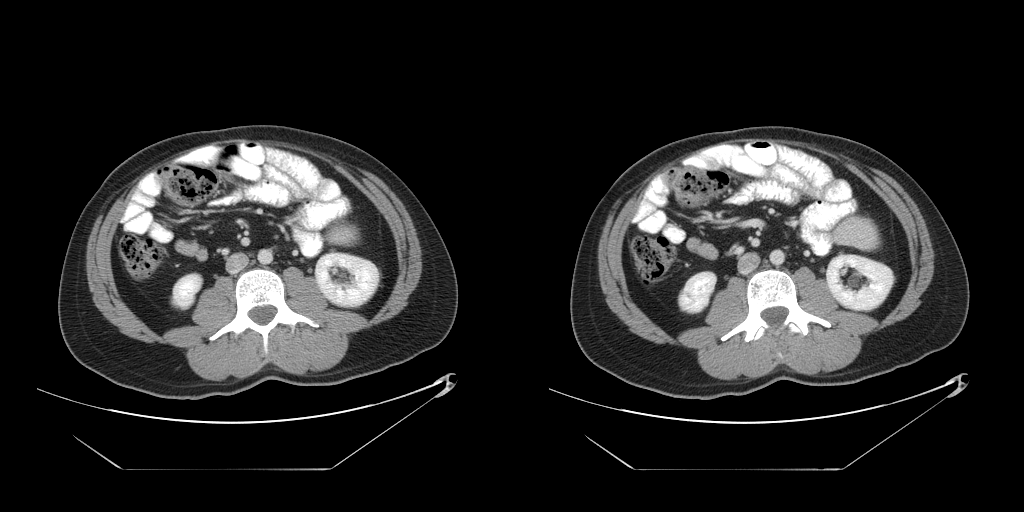

Results for the segmentation step in isolation using the selected models on the test partition of Dataset A are shown in Table 2. The Dice similarity coefficient (DSC) is used to measure the difference between the automatic segmentation and the manual ground truth. Our results improve upon those of Lee et al. [7], who had an average DSC of 0.93 for muscle, suggesting that the additional representational power of the U-Net and the more informative three-class training labels were effective at improving network accuracy. Additionally, our results improve upon those of Popuri et al. [11] who achieved Jaccard indices of 0.904 for muscle, and 0.912 for fat (visceral and subcutaneous as a single class) which correspond to DSC values of 0.950 and 0.954.

The full validation was then performed on Dataset B treating the two models as a single process that takes in a full abdominal CT series and produces estimates of body composition in terms of square cross-sectional area of muscle, subcutaneous fat, and visceral fat. In this case, the DSC is not an appropriate measure because the segmentation may be performed on a different slice from the ground truth mask. Table 2 compares the accuracy of the different tissue types and Figure 3 shows some example outputs.

The mean absolute localization error on the Dataset B test set was , which lies within the range of the L3 vertebra on the majority of patients.